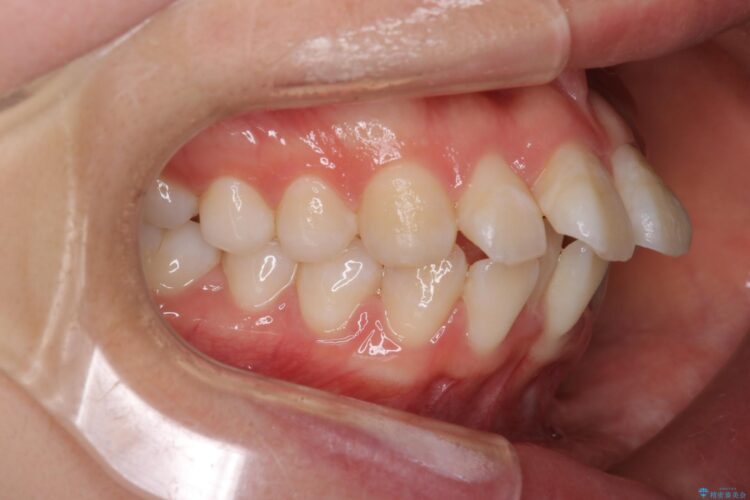

前歯のガつきと口元が出ていることを気にされご来院された患者様です。

治療計画

上下4番目の歯を抜歯してガタつきを改善しながら口元を下げる治療計画を立てました。